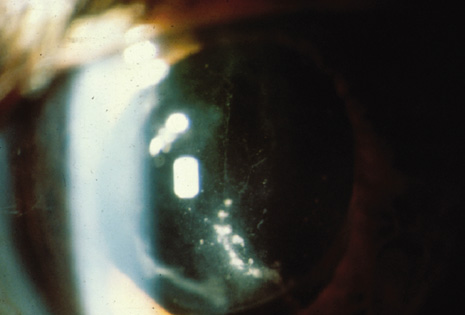

In this endophthalmitis category, patients may present weeks to months after cataract extraction, often with mild-to-moderate inflammatory signs and a chronic indolent course.16,94 P. acnes, a gram-positive, anaerobic pleomorphic rod, is a common causative organism in this category. The clinical P. acnes syndrome of delayed-onset pseudophakic endophthalmitis, first described by Meisler and associates94 in 1986, typically includes granulomatous inflammation with large keratic precipitates (Fig. 6) and a white intracapsular plaque that has been shown to be composed of organisms mixed with residual lens cortex. When infection with this slow-growing organism is suspected, anaerobic cultures of both the aqueous and vitreous should be obtained and held at least 2 weeks.

Fig. 6. Delayed-onset pseudophakic endophthalmitis. Left: This patient presented with granulomatous uveitis, vitritis, and a white plaque within the capsular bag, which is characteristic of infection caused by Propionibacterium acnes. Right: Marked granulomatous keratic precipitates are occasionally seen in endophthalmitis caused by P. acnes.